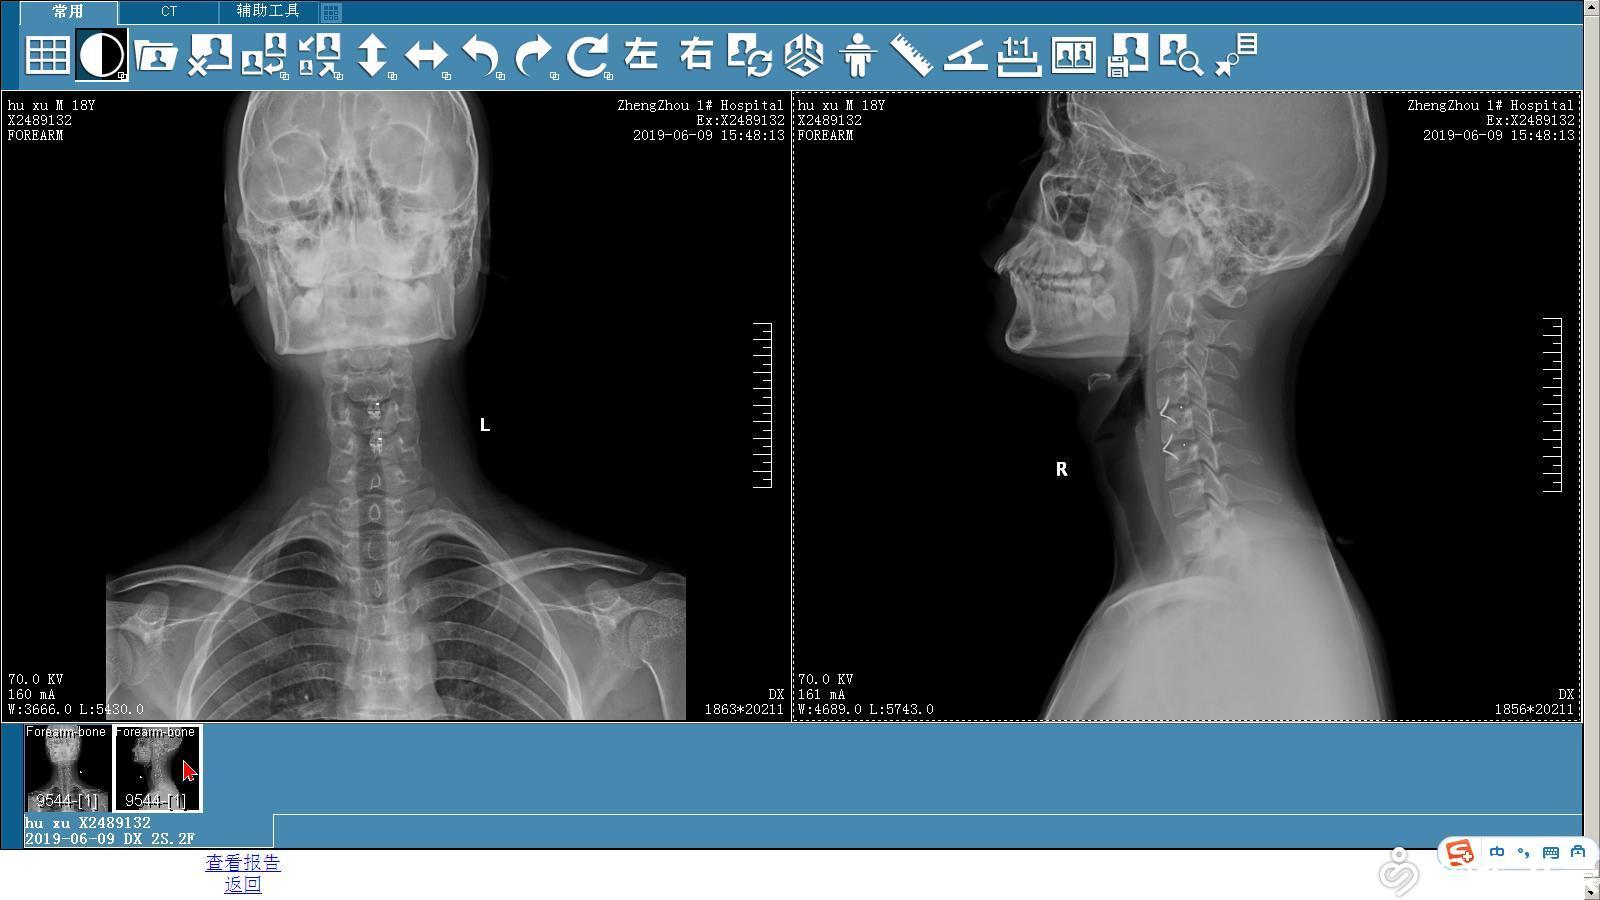

「平山病」—脊柱外科医生需要认识的一种"新疾病"

图片尺寸1225x445